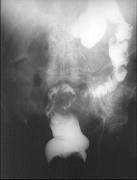

问题 女,50岁,便血10余年,加重1年(连续出血),近2个月大便时肛门常滴鲜血,量较多,X线检查如图,最可能的诊断是()

选项 A.直肠癌 B.直肠绒毛状腺瘤 C.直肠淋巴瘤 D.直肠转移瘤 E.直肠结核

答案 B